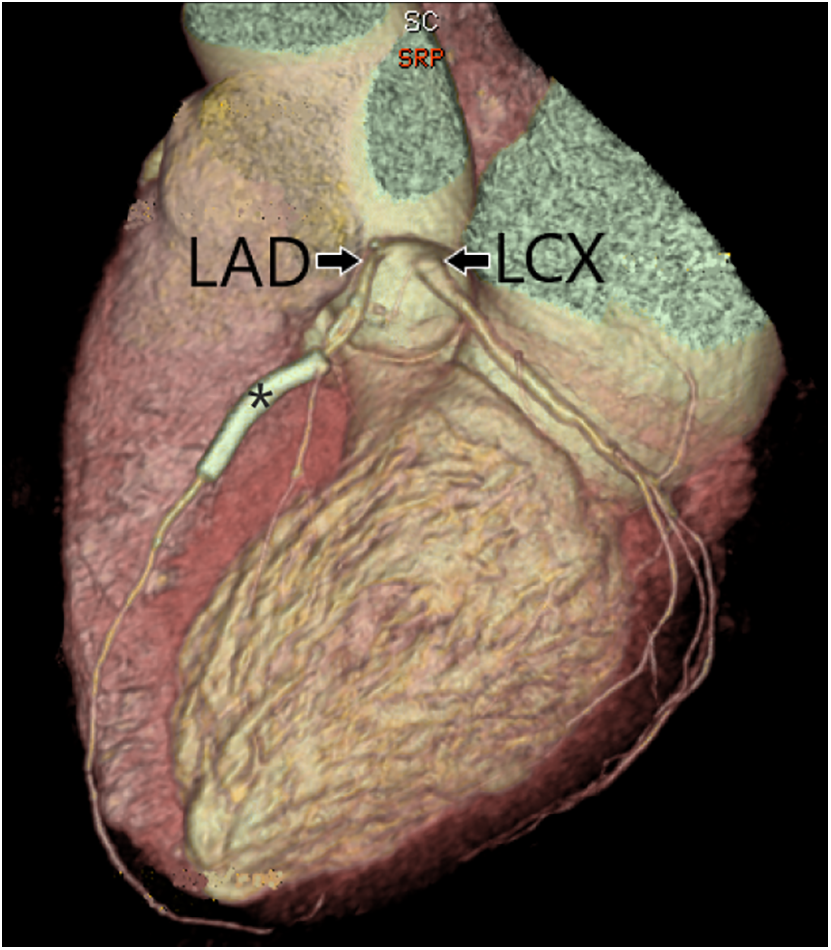

Coronary artery anomalies (CAAs) were classified into five groups. Group 1 included anomalies of the origin of the coronary arteries, defined as an origin, not from the corresponding sinus of Valsalva or higher than the junctional zone. Absent LMCA, with two separate origins of LAD and LCX, was classified in group 1 (Fig. 2).

Figure 2: Three-dimensional surface rendering of coronary CT angiography showing two separate origins of the left anterior descending artery (LAD) and left circumflex artery (LCX) from the left coronary cusp, with an absent left main coronary artery. Stent (*) is present in the LAD